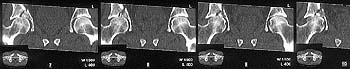

The iliac oblique reveals a displaced fracture of the posterior column, and it appears that the femoral head is not congruous with the acetabulum.

The CT scan confirms what the iliac oblique showed - the acetabulum is incongruous, and the femoral head is following the caudal piece medially. The other thing the femoral head is doing is grinding up against that displaced fracture. This is going to lead to erosion of the femoral head cartilage, and rapid onset of post-traumatic arthritis.

Yes it does. The CT scan reveals a fracture through the weight bearing dome.

My mail was based on the first mail from Alo Kullerkann before the CT pictures were avilable on the net. Later I saw the CT pictures and realised that weight bearing areas were involved.